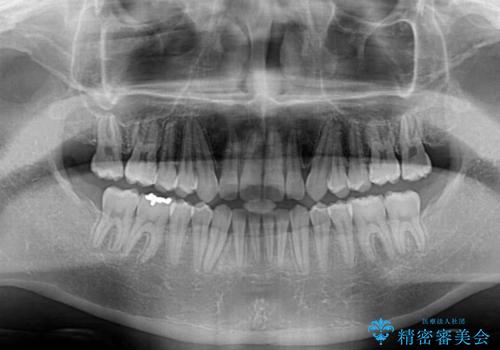

- 前歯の隙間と深い咬み合わせを改善したいとのことで来院された患者様です。

奥歯の咬み合わせは理想的な状態であったため、ワイヤー矯正でもインビザラインでも比較的容易に対応可能でした。